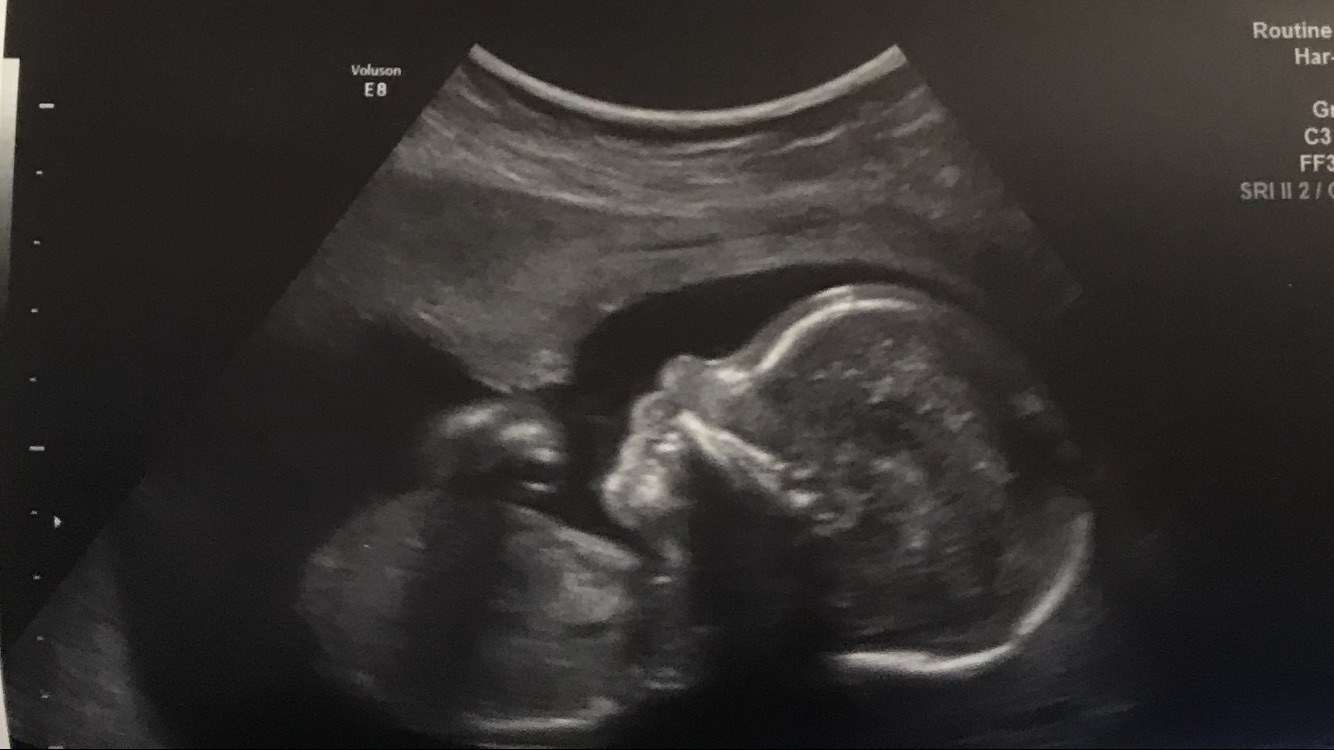

20 weeks in this ultrasound. We are not finding out gender but just wanted to see what y’all though about skull :)